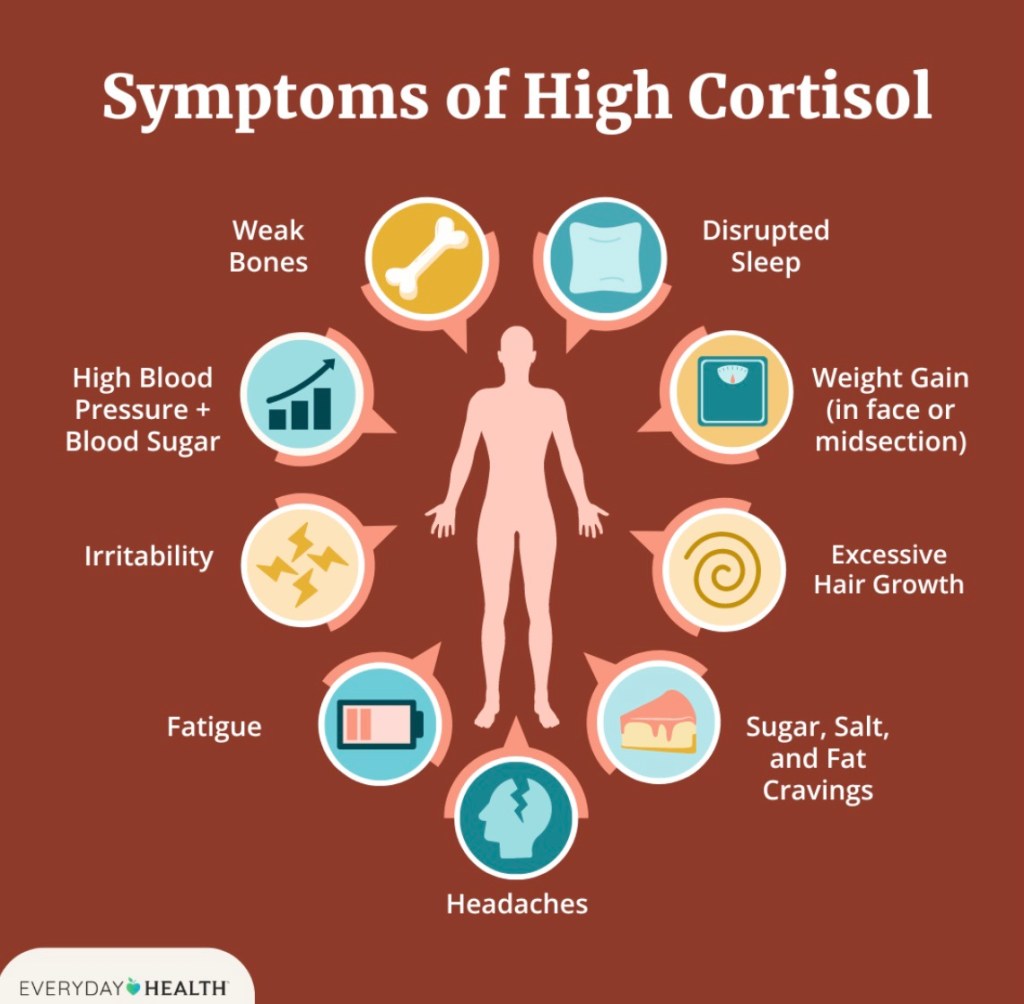

It took 3 months and more for the cortisol levels to come down to a point where he could safely sleep.

When a stranger enters his vicinity the cortisone levels rise again and the same fears rise to the surface.